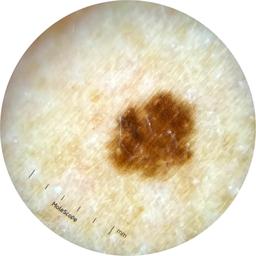

ISIC_5202282

IP_6423627

IL_0565396

Clinical

Field Value

acquisition_day 48

age_approx 50

anatom_site_1 Upper extremity

anatom_site_general upper extremity

diagnosis_1 Benign

diagnosis_confirm_type single image expert consensus

image_type dermoscopic